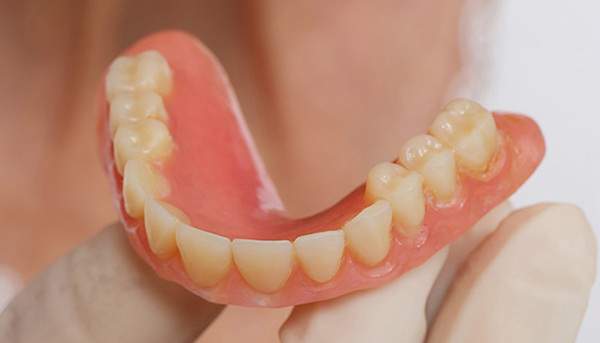

ケース1(自費の部分入れ歯)

前歯が折れて当院にいらっしゃいました。 過去に下の入れ歯を作ったが、合わなくなってずっと入れ歯をいれていらっしゃらない患者様でした。 これは奥歯で噛むことができないため、前歯で噛むことを繰り返したために、負担に耐えられなくなった前歯が折れてかぶせ物ごと 外れてしまったのだと考えられます。 痛くない、違和感の少ない、下の入れ歯を作ることがこの方のゴールであると考えられました。

シリコンで精密な型取りを行いました。

噛み合わせチェックです。 奥歯でしっかりものが噛める様に高さを決めていきました。

金属を使用して、薄く違和感が少ない入れ歯が完成しました。 また、見た目にも気を使い、バネが見えにくい様な構造にしました。

入れ歯をお口の中にいれた状態です。前歯もMTMといって、歯を少し引っ張り出す処置を行なったことで、しっかり残せて、またかぶせ物をしました。

年齢 70歳・女性

主訴 前歯が取れた

治療期間 8ヶ月

治療費 .MTM:110,000円

.ファイバーコア:16,500円

.E-maxクラウン:110,000円

.義歯:660,000円

治療方針 長年使ってきた義歯の人工歯が磨耗し、臼歯部での咬合がすくなくなり、前歯部での接触が強くなったことで生じた前歯の破折なので、義歯も作り変える必要がある。

治療内容 前歯部MTMと同時に審美面の回復。

MTM中に義歯の作成も同時に行う。

最終的に義歯と前歯のクラウンを同時にいれる。

義歯は下顎で、しっかり噛めること、違和感の少ないものという希望があったため、なるべく入れ歯を薄く作成するために金属をしようした義歯とした。

また、見た目もあまり義歯が目立たない様に、バネの部分を見えにくいように作成した。

特記事項 歯にもともと入っていた金属の種類によっては、歯自体の変色を治療で変えられないこともある。 義歯は作ってから痛みがでることがありますが、それは調整を行うことで痛くなくすることができます。